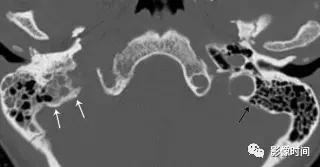

3、脑膜瘤:脑膜瘤是中枢神经系统最常见的脑外颅内肿瘤,大多数脑膜瘤发生在颅内。颈静脉孔区的脑膜瘤可向下延伸至颈动脉间隙。大多数脑膜瘤 CT 表现为等或者高密度,20% 钙化,邻近骨质表现为反应性骨质增生。在 MRI 上,脑膜瘤通常表现为 T1WI 等或稍低信号,T2WI 等或稍高信号,明显强化,可见脑膜尾征。

轴位 CT 显示病灶相邻的骨质增生(白色箭头),正常左乳突骨皮质 (黑箭头)。轴位 T2WI 病灶呈等信号 (白色箭头),向前推移颈内动脉 (i)。左侧颈内动脉的正常位置也被观察到。

矢状位 T1WI+C 病灶明显强化 (白色箭头) 从后窝延通过颈静脉孔 (黑色箭头) 延伸至右颈动脉间隙,见硬膜尾征(无尾箭头)。